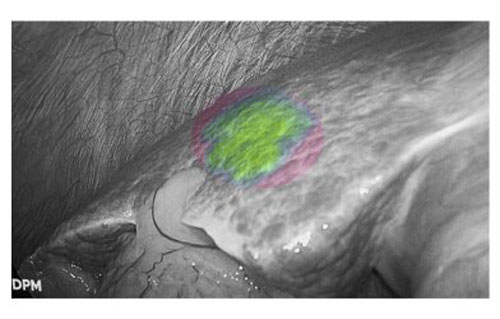

肝癌患者多合并肝硬化背景,而腹腔镜手术因缺乏触觉反馈,致使术者在微创条件下难以识别隐匿性病灶。吲哚菁绿(ICG)荧光显影技术通过术前静脉注射造影剂,可精准定位3毫米的原发性肝癌和肝转移癌。该技术有效弥补了腹腔镜肝胆手术中触觉反馈缺失的固有缺陷,为微创精准外科提供了重要技术支撑。

荧光显影技术,可精确显示肝内隐匿病灶

患者肝右后叶肝癌,根据三维重建精准阻断右后肝蒂,获得缺血线后进行荧光反染,显示肝脏切面的荧光和非荧光界面,助力解剖性肝右后区切除。

三维重建技术直观呈现肝段划分及血管、胆管解剖关系,而荧光显影技术则通过肝段染色,全程显露段间静脉,有助于识别肝内肝段间的界限,使肝胆外科医师可以全程实时观察肝脏切面变化,及时作出调整,优化手术方案,实现真正意义上的解剖性精准治疗。此外,吲哚菁绿(ICG)经胆道排泄的特性使术中胆管结构呈现清晰绿色荧光,大幅提升胆总管辨识度,有效降低腹腔镜手术中胆管损伤风险,为复杂肝胆手术安全性再添保障,显著降低了胆管损伤及相关并发症的发生率,进一步提升了手术安全性。